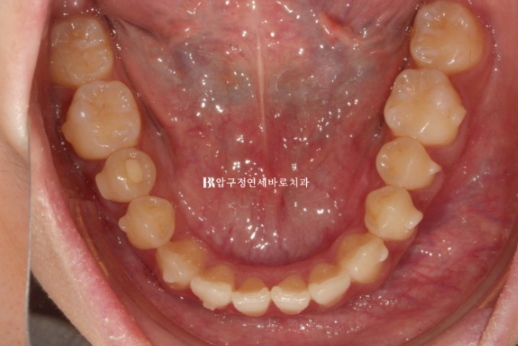

올해 2월, 앞니 덧니를 치료하고자 오신 환자분입니다.

앞에서 보면 별 문제가 없어보이지만,

앞니 두개가 튀어나온 토끼이빨이며 특히 우측 앞니가 많이 들려있습니다.

어금니 교합은 좋은 상태라서 인비절라인 익스프레스를 권유드렸습니다.